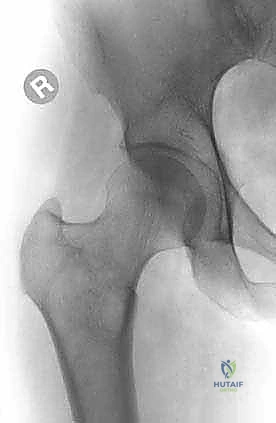

- الأشعة السينية العادية (X-rays): هي الخطوة الأولى دائماً. تظهر النقائل الحالة للعظم كبقع داكنة (ثقوب) في العظم، بينما تظهر النقائل البانية كبقع بيضاء كثيفة. الأشعة السينية ضرورية لتقييم خطر الكسر.

1. الجزء العلوي من عظم الفخذ (Proximal Femur)

هذه المنطقة هي الأكثر عرضة للإصابة بالنقائل العظمية، وهي تتحمل أكبر قدر من الإجهاد الميكانيكي أثناء الوقوف والمشي. تتكون من رأس الفخذ، عنق الفخذ، والمدورين (الكبير والصغير).

- مفصل الورك ومحفظة المفصل: رأس الفخذ يتمفصل مع الحُق (Acetabulum) في الحوض لتكوين مفصل الورك. يحيط بهذا المفصل محفظة ليفية (Capsule) سميكة جداً توفر الثبات. عند انتشار الورم في عنق الفخذ، يزداد خطر حدوث كسر بشكل كبير جداً، مما يتطلب تدخلاً عاجلاً.